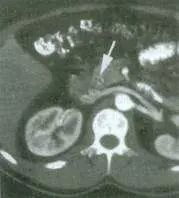

60 歲女性因急性腹痛、發燒至急診處,血液檢查結果為 bilirubin (total/direct ): 3.5/2.0 mg/dL ,AST :100 U/L ,ALT :75U/L ,腹部電腦斷層結果如圖,最可能的診斷為:

腹部電腦斷層(CT)橫切面影像顯示:

- 白色箭頭指示區域:影像中央可見一白色箭頭指向腹部中央偏左上方的結構,可辨識出一條圓形低密度管腔結構(tubular hypodense structure),此為**擴張的總膽管(dilated common bile duct)**或膽道系統

- 膽管擴張(biliary dilatation):正常 CBD 直徑應 < 8 mm(未曾接受膽囊切除者),影像所見管腔明顯擴大,符合**膽管阻塞(biliary obstruction)**的影像特徵

- 整體腹腔結構:可見肝臟(右側高密度區域)、脊椎及周邊組織,無明顯腹水或實質臟器異常密度

- 臨床意義:擴張的膽管合併發燒、黃疸、腹痛,強烈支持**膽道感染(biliary infection)/ 急性膽管炎(acute cholangitis)**的診斷